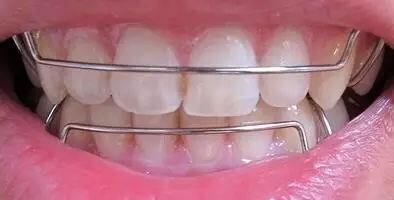

我剛帶上牙套的一周內(nèi),需要注意的事情有很多,值得慶幸的是沒有滿嘴的鋼絲。這一周內(nèi)牙齒并沒有什么明X的變化,就只是牙齒吃東西的時(shí)候會(huì)有些不舒服的感覺,可能是剛帶牙套的關(guān)系吧。

牙齒矯正術(shù)后一個(gè)星期